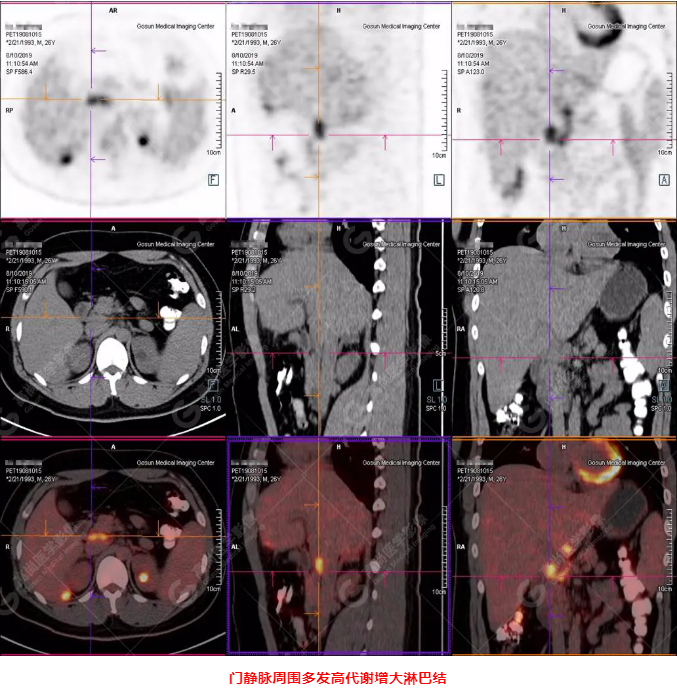

B超及CT檢查發(fā)現(xiàn):肝臟多發(fā)低密度占位。

PET/CT全身圖

PET/CT診斷

嗜酸性粒細(xì)胞增多癥肝浸潤

5.嗜酸性粒細(xì)胞增多肝浸潤同白血病浸潤類似,主要表現(xiàn)多發(fā)性、結(jié)節(jié)性浸潤,伴肝大,單發(fā)浸潤少見